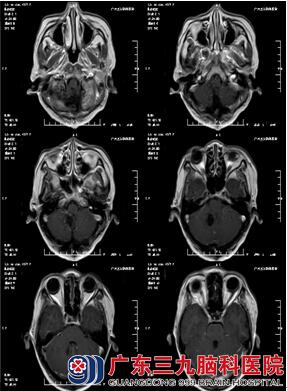

47岁的林女士,因“头痛伴呕吐20天” 到广东三九脑科医院住院治疗。林女士曾在当地医院做CT检查,提示:右侧小脑占位性病变,考虑为血管母细胞瘤。当地医院予对症处理,呕吐症状稍缓解,但头痛症状无明显缓解。现为行手术治疗来我院就诊,门诊拟“右侧小脑占位性病变”收治入院。

入院后完善术前准备后,由林涛主任主刀在全麻下行“脑干背侧血管母细胞瘤切除术”,术中见肿瘤位于脑干背侧,囊性为主,脑组织张力较高,释放囊液后,探及肿瘤,鲜红色改变,血供较丰富,大部分间隙清晰,与脑干少许粘连。术中给予镜下逐步分离并全切除肿瘤,病理提示:血管母细胞瘤(WHO I级)。手术顺利,术后给予预防感染、止血、神经营养支持、预防应激反应及全身营养支持等综合观察治疗。经10多天治疗,林女士头痛明显减轻,病情康复出院。

在外周血象常规检查中,部分患者有血红蛋白和红细胞异常增高,故检测外周血红细胞,血红蛋白对血管网织细胞瘤的诊治及预防有一定的参考价值。CT及MRI检查可明确诊断。颅后窝血管网织细胞瘤CT分型为:① 囊结型;②囊肿型;③实体型 ④脑积水型。CT平扫时呈现较均匀的低密度的结节,即瘤结节。增强扫描后瘤结节明显强化,而囊壁则无明显强化。本病应与囊性星形细胞瘤鉴别,后者囊壁多不光滑、规则,瘤结节大小不一、密度不均、边界不清,或有钙化。由MRI成像不受颅后窝骨伪影的影响,故对本病的检出率MRI高于CT,囊性病变在T1为低信号,T2为高信号,而瘤结节为等信号,Tz 为高信号,可在肿瘤周围看到 T2 相有水肿带。另外血管造影可见肿瘤结节的异常血管网或肿瘤结节染色。本病CTA典型表现为瘤结节为边缘整齐球形血管团,与1支动脉相连,动脉期可显影。